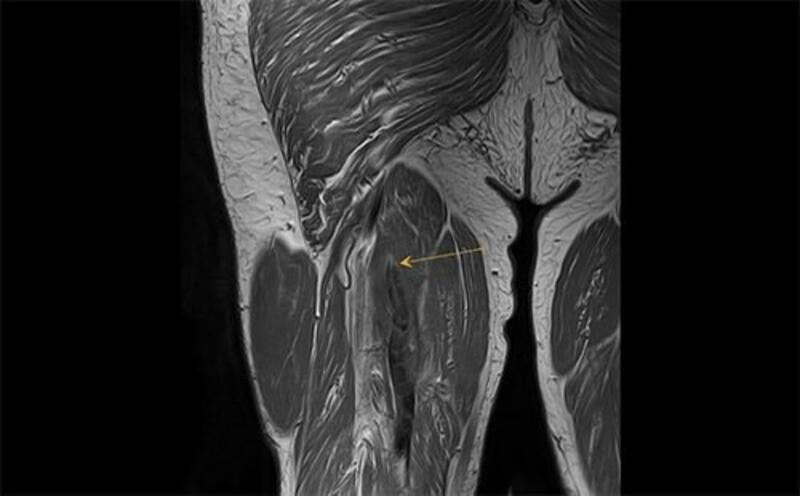

Al respecto, el doctor Mostien y sus compañeros del Hospital Jessa (en Hasselt-Bélgica) y la Universidad de Hasselt tomaron biopsias musculares de pacientes con Covid en estado crítico antes y después de la admisión a cuidados intensivos. Un total de 18 pacientes fueron analizados para el proyecto. Concretamente su vasto lateral, el músculo más grande y poderoso del muslo, biopsiado varias veces desde 1-3 días antes de la admisión en la UCI hasta 5-8 días después de la admisión. Los pacientes tenían una edad media de 69 años y el 82 por ciento eran hombres.